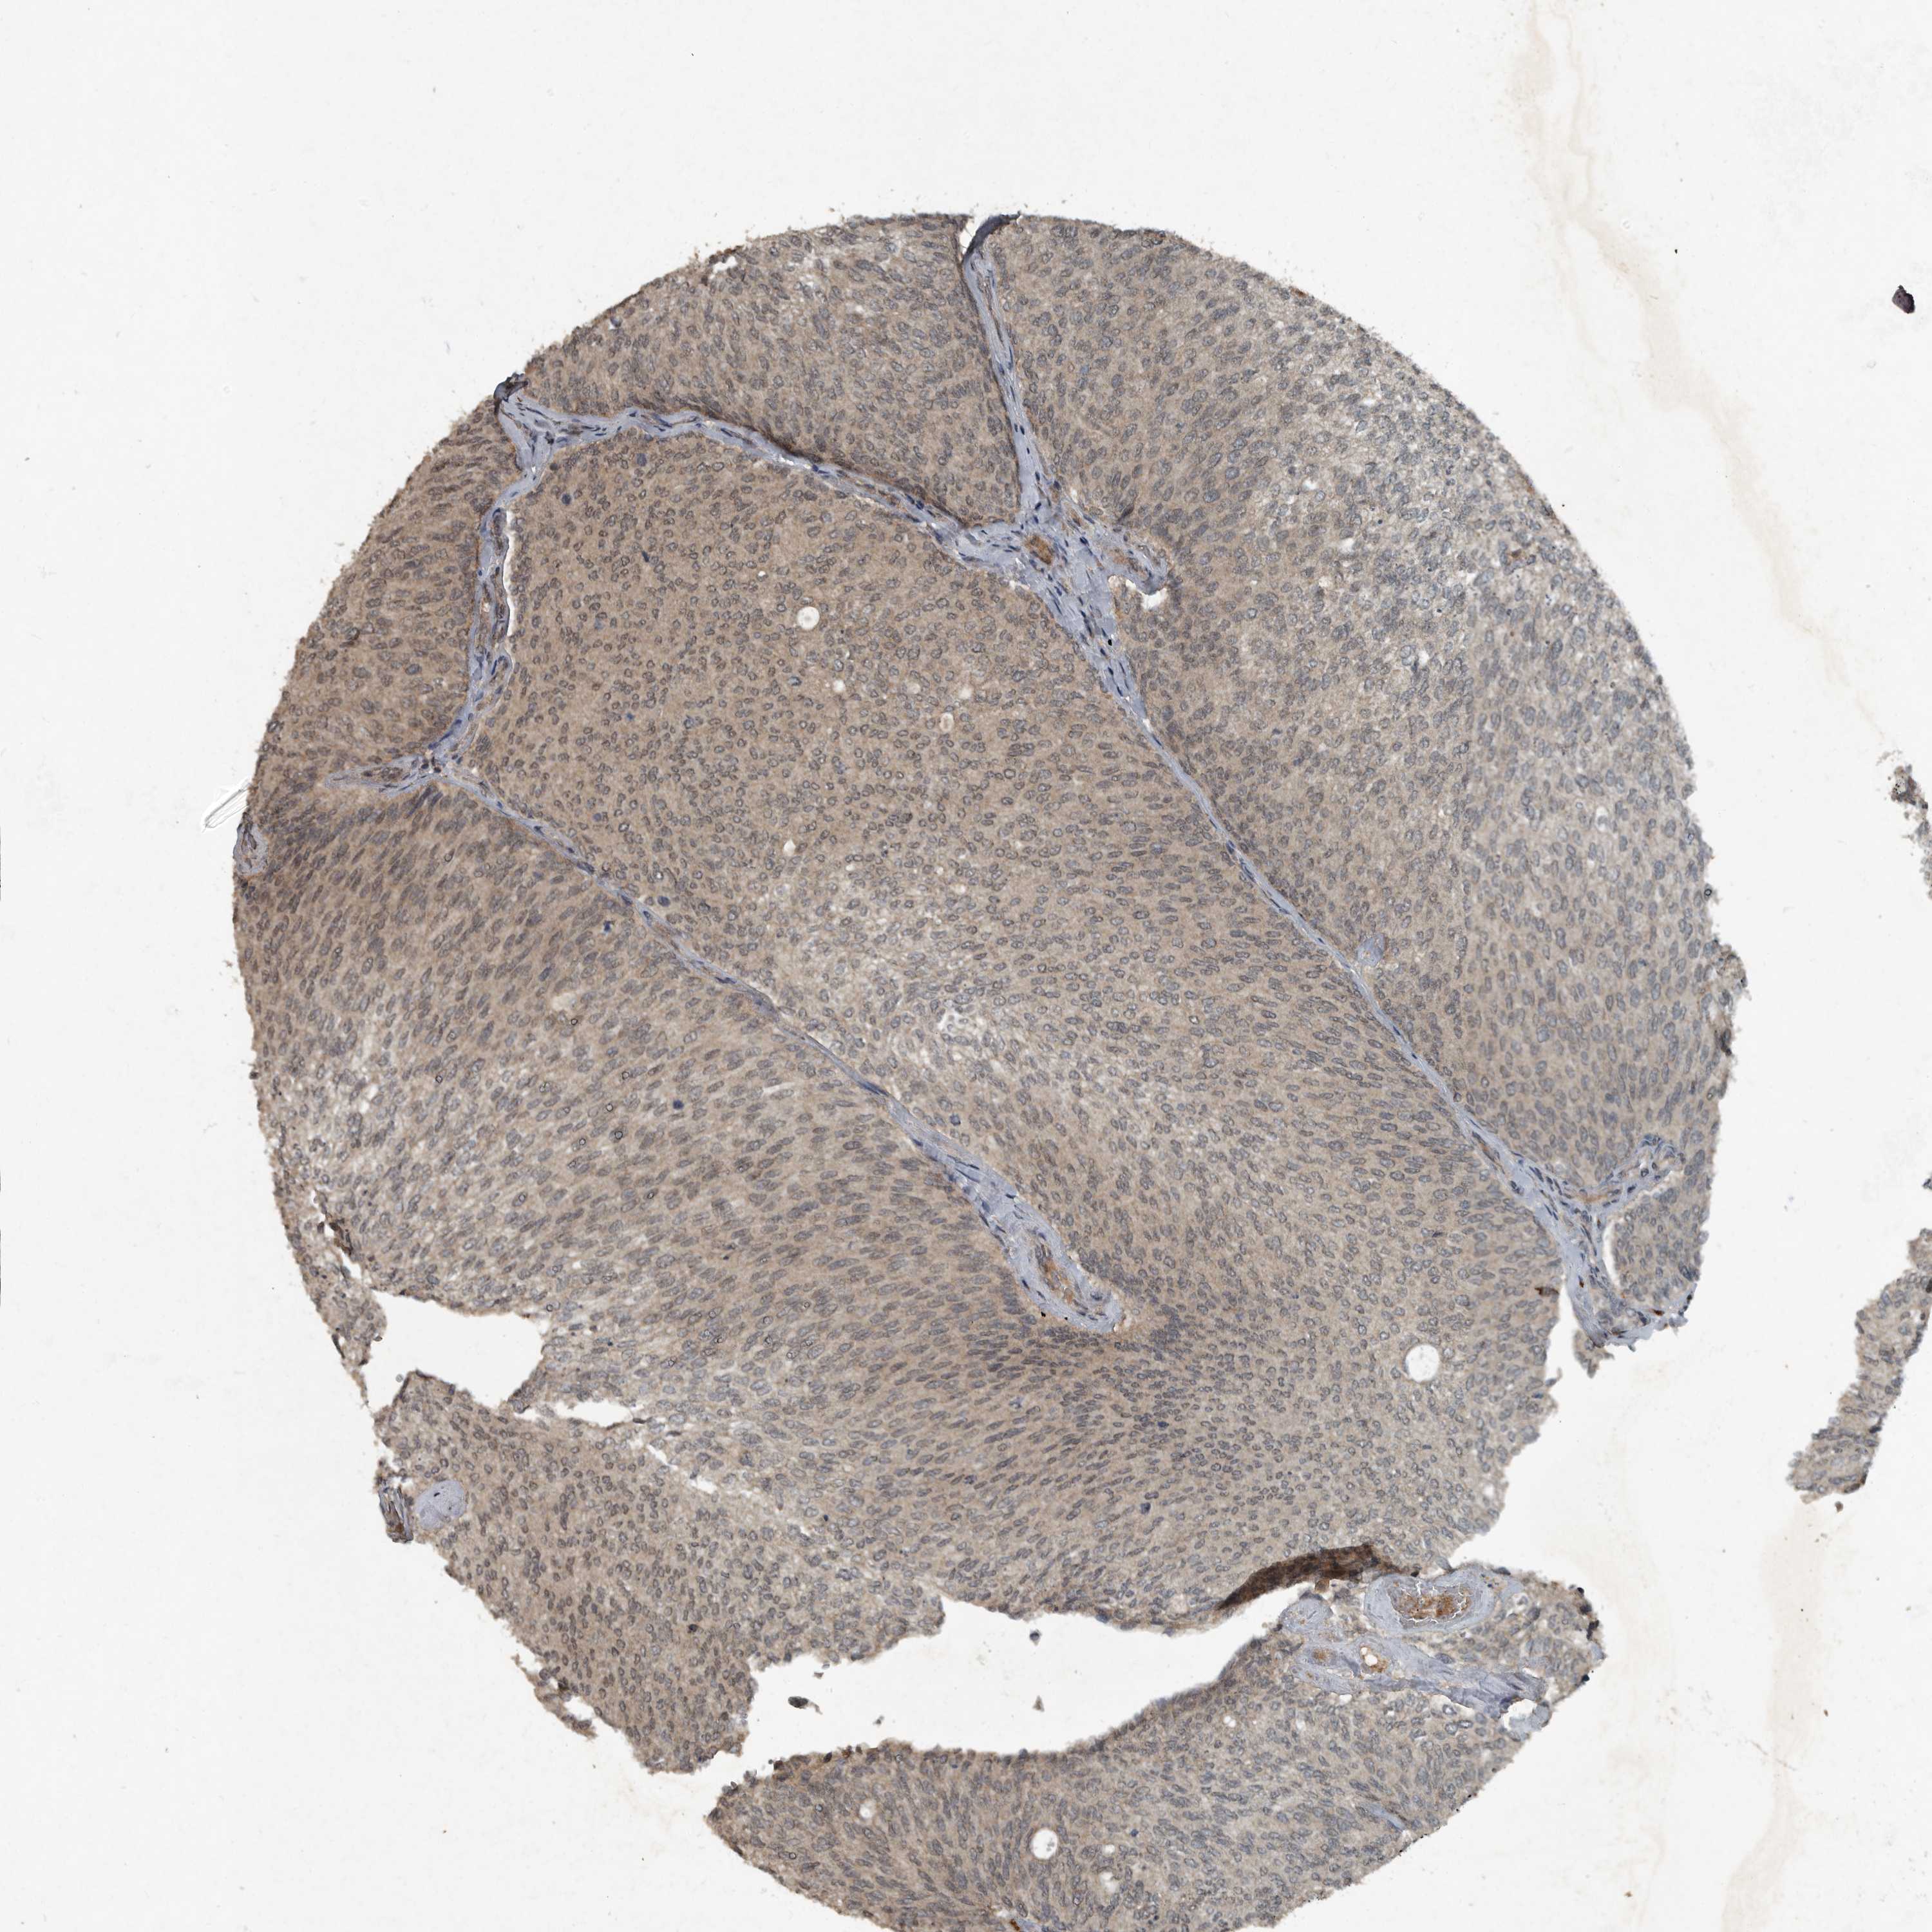

UROTHELIAL CANCER - Protein expressioni

A mouse-over function shows sample information and annotation data. Click on an image to view it in a full screen mode. Samples can be filtered based on level of antibody staining by selecting one or several of the following categories: high, medium, low and not detected. The assay and annotation is described here.

Note that samples used for immunohistochemistry by the Human Protein Atlas do not correspond to samples in the TCGA dataset.

Antibody stainingi

Antibody staining in the annotated cell types in the current human tissue is reported as not detected, low, medium, or high, based on conventional immunohistochemistry profiling in selected tissues. This score is based on the combination of the staining intensity and fraction of stained cells.

Each image is clickable and will lead to virtual microscopy that enables deeper exploration of all samples and also displays staining intensity scores, fraction scores and subcellular localization as well as patient and tissue information for each sample.

HPA001252

Urothelial carcinoma, High grade

Urothelial carcinoma, Low grade

Adenocarcinoma, NOS